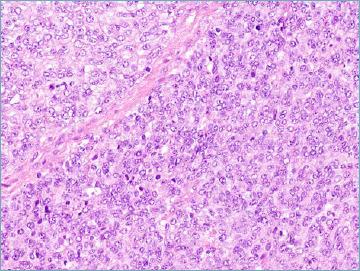

Mesenchymal tumours represent one of the most challenging field of diagnostic pathology and refinement of classification schemes plays a key role in improving the quality of pathologic diagnosis and, as a consequence, of therapeutic options. The recent publication of the new WHO classification of Soft Tissue Tumours and Bone represents a major step toward improved standardization of diagnosis. Importantly, the 2020 WHO classification has been opened to expert clinicians that have further contributed to underline the key value of pathologic diagnosis as a rationale for proper treatment. Several relevant advances have been introduced. In the attempt to improve the prediction of clinical behaviour of solitary fibrous tumour, a risk assessment scheme has been implemented. NTRK-rearranged soft tissue tumours are now listed as an "emerging entity" also in consideration of the recent therapeutic developments in terms of NTRK inhibition. This decision has been source of a passionate debate regarding the definition of "tumour entity" as well as the consequences of a "pathology agnostic" approach to precision oncology. In consideration of their distinct clinicopathologic features, undifferentiated round cell sarcomas are now kept separate from Ewing sarcoma and subclassified, according to the underlying gene rearrangements, into three main subgroups (CIC, BCLR and not ETS fused sarcomas) Importantly, In order to avoid potential confusion, tumour entities such as gastrointestinal stroma tumours are addressed homogenously across the different WHO fascicles. Pathologic diagnosis represents the integration of morphologic, immunohistochemical and molecular characteristics and is a key element of clinical decision making. The WHO classification is as a key instrument to promote multidisciplinarity, stimulating pathologists, geneticists and clinicians to join efforts aimed to translate novel pathologic findings into more effective treatments.